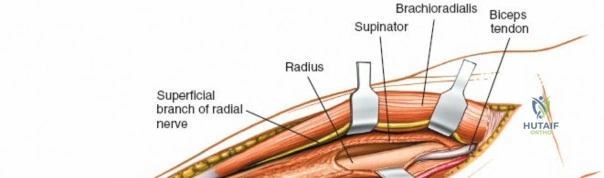

Superficial Surgical Dissection and Internervous Plane

Incise the deep fascia of the forearm in line with the skin incision. The initial goal is to identify the medial border of the brachioradialis as it courses down the forearm. It is a common pitfall to search for this border too far laterally. At the level of the elbow, the brachioradialis is expansive and extends almost halfway across the anterior forearm. It is surprisingly easy to mistake the plane between the brachioradialis and the extensor carpi radialis longus for the correct intermuscular plane.

To confirm the correct plane, look for the superficial branch of the radial nerve. This sensory nerve runs on the undersurface of the brachioradialis muscle. Once the true medial edge of the brachioradialis is found, develop the plane between it and the pronator teres (proximally) or the flexor carpi radialis (distally). Retract the brachioradialis laterally, taking care to keep the superficial radial nerve attached to its undersurface to protect it from traction injury.

Managing the Radial Artery and Recurrent Leash

As the brachioradialis is retracted laterally, the radial artery and its venae comitantes are exposed lying deep in the middle part of the forearm, closely related to the medial edge of the wound. Begin dissection distally and work proximally. Just below the elbow joint, the radial artery gives off the recurrent radial artery and a leash of muscular branches that dive laterally into the brachioradialis.

This leash must be meticulously managed. Take time to isolate, ligate, and divide these vessels. Do not attempt to use electrocautery alone on the larger branches, and absolutely avoid blunt avulsion. Avulsion of these vessels from the main radial artery is a potent cause of difficult-to-control intraoperative bleeding and severe postoperative hematoma. Once the leash is divided, the brachioradialis can be fully mobilized laterally, exposing the deep muscular layer.